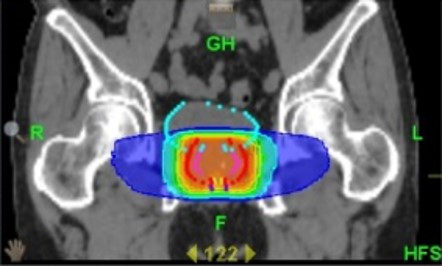

■放射線治療(外照射療法): 外部から放射線を照射し、がんを死滅させる治療法です。現在は、高精度放射線治療である強度変調放射線治療(IMRT)が標準的な治療法とされています。IMRTでは正常組織の被曝を最小限にしつつ、がん組織に放射線を集中的に照射することが可能です。